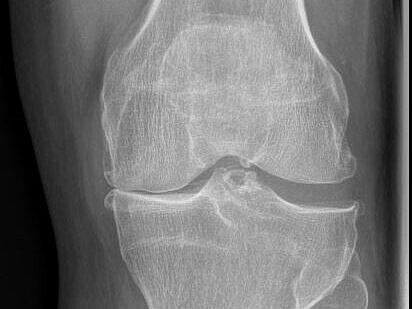

Arthrose des Knie-Gelenks

Arthrose des Knies, auch als Kniegelenksarthrose bekannt, ist eine degenerative Erkrankung, die durch den Verschleiß des Knorpelgewebes im Kniegelenk gekennzeichnet ist.

Dies kann zu Schmerzen, Steifheit und eingeschränkter Beweglichkeit führen und die Lebensqualität erheblich beeinträchtigen.

Röntgen

Schnelle und präzise Diagnosen direkt vor Ort verkürzen nicht nur die Wartezeiten für die Patienten, sondern ermöglicht auch eine effiziente und nahtlose Versorgung.